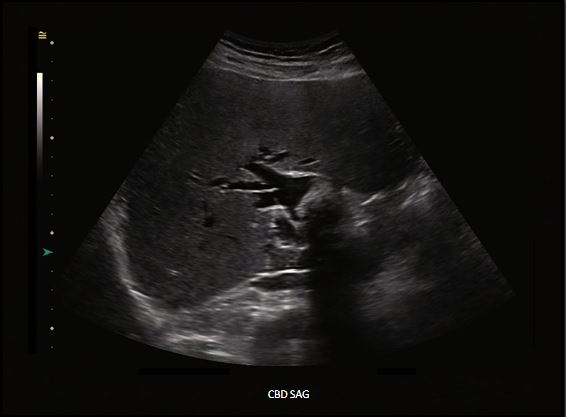

A patient with right upper quadrant pain, nausea, and vomiting presented for an ultrasound evaluation. IMAGING FINDINGSThe right upper quadrant ultrasound revealed a large shadowing structure in the abnormally dilated proximal CBD with associated intrahepatic biliary duct dilatation. Findings suggest a large CBD stone vs. partially calcified mass.

FINAL DIAGNOSIS: Large CBD stone (choledocholithiasis).CBD SAGCholedocholithiasis is a condition defined by the presence of stones within the common bile duct (CBD). Depending on the stone origin, choledocholithiasis is classified as primary or secondary. When the stones are formed directly within the biliary tree, the condition is referred to as primary choledocholithiasis. In contrast, the condition is called secondary choledocholithiasis, when the stones are formed in the gallbladder and ejected into the biliary tree following the gallbladder contractions.Primary choledocholithiasis is typically composed of brown stones and is rare in Western populations. Brown stones are commonly found in the extrahepatic and intrahepatic ducts in the presence of biliary stasis and bacterial infection. Bacterial by-products in the bile stasis environment cause precipitation of bilirubin out of solution, leading to a formation of brown stone. Secondary choledocholithiasis is the most common form of the condition. It results from the passage of stones formed in the gallbladder into the cystic duct and then into the common bile duct. These stones are typically composed of cholesterol. 95

As mentioned earlier, in the vast majority of choledocholithiasis cases, the stones form within the gallbladder and then migrate into the CBD due to gallbladder contractions. Once lodged in the CBD, the stones may disrupt the normal bile flow and cause various problems, including severe right upper quadrant pain, nausea, vomiting, biliary obstruction, and jaundice. Biliary obstruction and stagnant bile may lead to the colonization of bile by microorganisms resulting in bile infection and consequent ascending cholangitis. CBD SAGA large shadowing structure in the abnormally dilated proximal CBD with associated intrahepatic biliary duct dilatation represents choledocholithiasis.96

A confirmatory diagnosis of choledocholithiasis is made with advanced imaging, including magnetic resonance cholangiopancreatography (MRCP) and endoscopic retrograde cholangiopancreatography (ERCP). A transabdominal ultrasound is typically the first imaging test that is ordered for the patient suspected of any biliary disease. Like gallbladder stones, biliary stones appear echogenic and round-shaped. They often cast dense posterior acoustic shadowing and can be mobile. Unfortunately, ultrasound is significantly less accurate in detecting stones in the CBD than detecting stones in the gallbladder.CBD SAGAbnormally dilated CBD measuring up to 3 cm with approximately 2.6 cm shadowing structure identified centrally is choledocholithiasis.97